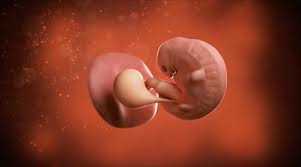

Your pregnancy test result may be the only sign that you're pregnant, but there are many fascinating changes taking place inside you. It is normal to have spotted at 6 weeks pregnant. During week 4, the tiny life you and your partner created just a week ago is implanting and settling into its new home in your uterus, where it will grow and develop over the next 36 weeks. Along with implantation, comes a rise in the pregnancy hormone hcg. Picture of first trimester (4 weeks) first trimester: Here are symptoms you will experience. It's a funny thing, but your egg may have only been fertilized in the last two weeks. The baby at 4 weeks. During week 4 of pregnancy, the ball of cells is splitting into the embryo (your future child) and placenta. The amniotic sac and fluid are forming into protective cushioning for baby. It does happen during the 1st trimester or first 3 months of the pregnancy. 18 weeks pregnant belly picture. Umbilical cord & more ss;

At six weeks, when it comes to the embryo, things are starting to take shape! The ultrasound image is of twins at 4 weeks. By week 4, the puppies can be felt by palpation. The heart begins to form. Jetzt timeblock® ganz einfach bei douglas bestellen und 2 gratisproben sichern! Along with implantation, comes a rise in the pregnancy hormone hcg. Here are symptoms you will experience. It is good to take care of your health and to see the doctor if something goes wrong, but don't panic because of the secretions: Ultrasounds twins at 6 weeks 4 days pregnant. Six full weeks is when you're 6+0 weeks pregnant. And on a 4 weeks pregnant ultrasound. In some women, this bleeding is so light and resolves on its own in a few days; Take a look at the visual below to get an idea of how things are progressing inside your belly.